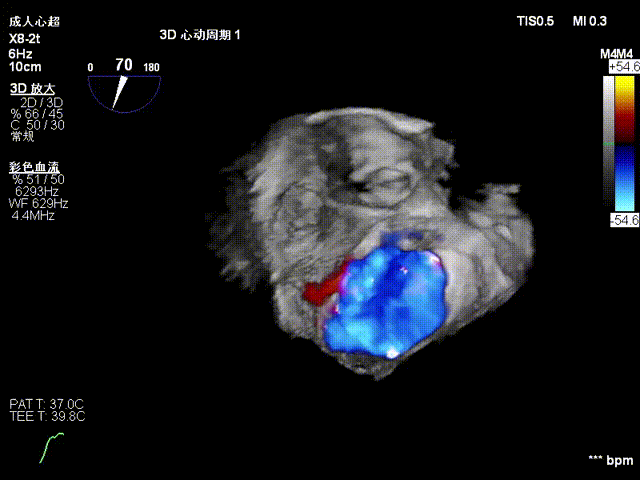

第二枚瓣膜夹植入于P2残余脱垂处

术后二尖瓣反流降至微量,瓣膜夹稳定,功能良好

手术经股静脉-房间隔入路,采用全身麻醉插管,在TEE和DSA引导下完成房间隔穿刺。置入JensClip瓣膜夹系统后,在左房调整瓣膜夹的位置和轴向,后进入左室,在TEE引导下捕捉二尖瓣前后瓣叶,并关闭瓣膜夹。经TEE反复确认手术效果后最终锁定并释放瓣膜夹。由于该病例二尖瓣后叶P2区及部分P3区脱垂,脱垂范围宽度达20mm,术中植入了两枚长宽(LW)的瓣膜夹。术后即刻超声显示瓣膜夹位置稳定,功能良好,二尖瓣反流由术前4+减少至微量,肺静脉逆流和左房压都显著好转,手术圆满成功。术后患者状态良好,目前已安排出院。